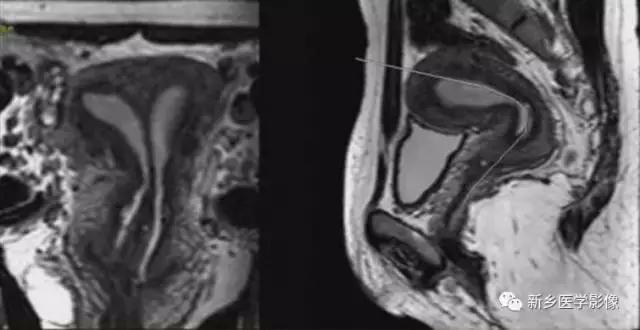

完全型纵隔子宫:短T2信号纵隔贯穿宫腔,宫颈管及阴道上段。

MR诊断为完全型纵隔子宫伴阴道纵隔。

完全型纵隔子宫:宫底平坦,纵隔贯穿宫腔和宫颈

不完全型纵隔子宫:宫底平坦,纵隔未达宫颈内口水平